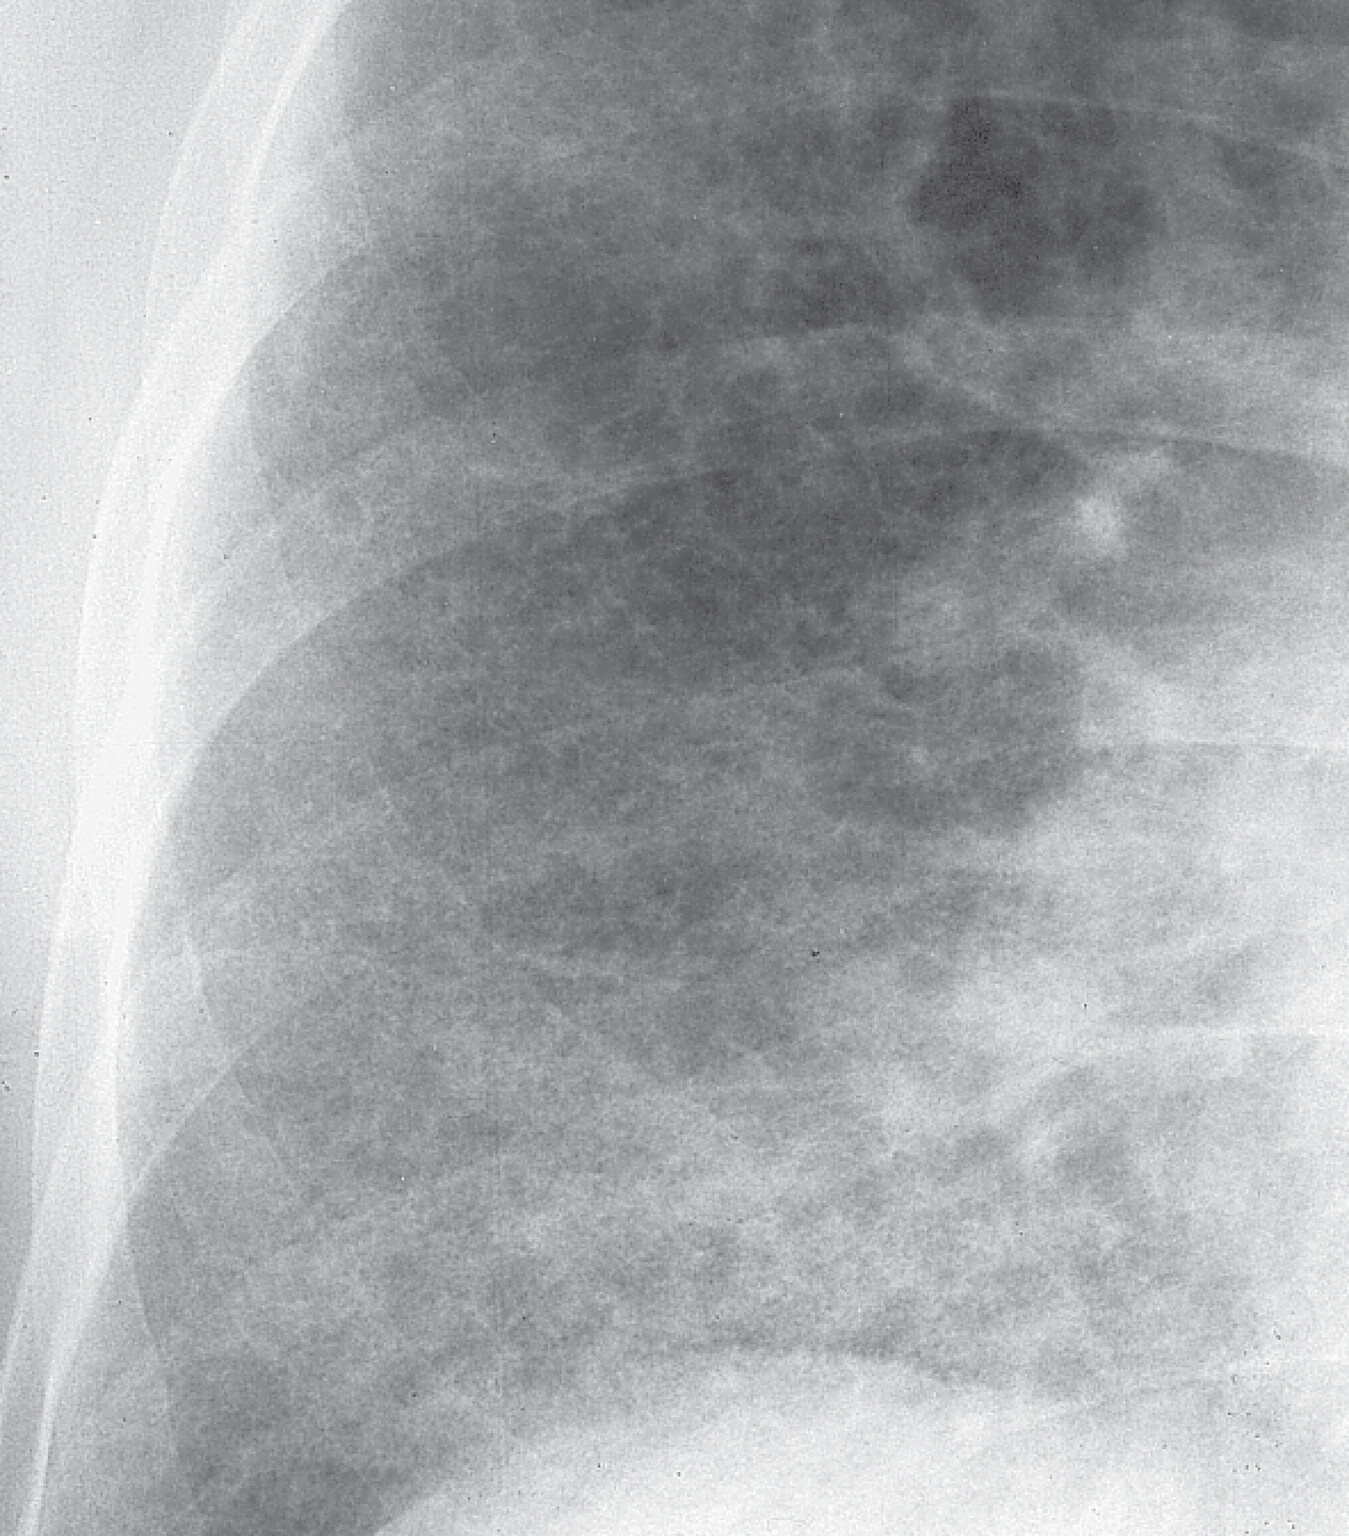

Besteht der Verdacht einer Sarkoidose, sollte eine Röntgen-Thorax-Übersicht durchgeführt werden. Die Lungensarkoidose kann nach dem Röntgen-Thorax-Befund in vier Röntgentypen eingeteilt werden (Abb. 27.8):

- Typ I: beidseitige Hilusadenopathie ohne pulmonale Beteiligungen

- Typ II: beidseitige Hilusadenopathie mit pulmonalen Beteiligungen

- Typ III: pulmonale Beteiligungen ohne Hilusadenopathie

- Typ IV: Zeichen der Lungenfibrose.

Bei Erkrankungen vom Typ I können bei 70–90% der Fälle innerhalb eines Jahres spontane Remissionen erwartet werden, vor allem, wenn ein Löfgren-Syndrom vorliegt (akute Sarkoidose). Beim Typ II findet man immerhin noch 50% Spontanremissionen.

Abb. 27.8 Sarkoidose

a Akute Sarkoidose Röntgentyp I. 38-jähriger Mann mit Reizhusten und beidseitiger Sprunggelenksarthritis. Röntgenologisch beidseitige Hiluslymphome, mäßige Verbreiterung des Mediastinums im rechten Tracheobronchialwinkel nach rechts durch Mediastinallymphome (→). Rückbildung der Gelenkbeschwerden nach 2-wöchiger Diclofenac-Therapie.

b Chronische Sarkoidose Röntgentyp II. 47-jährige Frau. Disseminierte kleinfleckig-streifige, z. T. konfluierende Konsolidierungen beider Lungen, geringe Hiluslymphome beidseits. Die Patientin ist symptomfrei.

c Chronische Sarkoidose Röntgentyp IV. 37-jährige Frau. Dichte beidseitige grobfleckig-streifige z. T. konfluierende Lungenverschattungen mit unscharfer Abgrenzung der Zwerchfelle, geringe Verdichtung und Kranialverziehung der Hili beiderseits. Die Patientin wurde durch Belastungsdyspnoe auffällig.